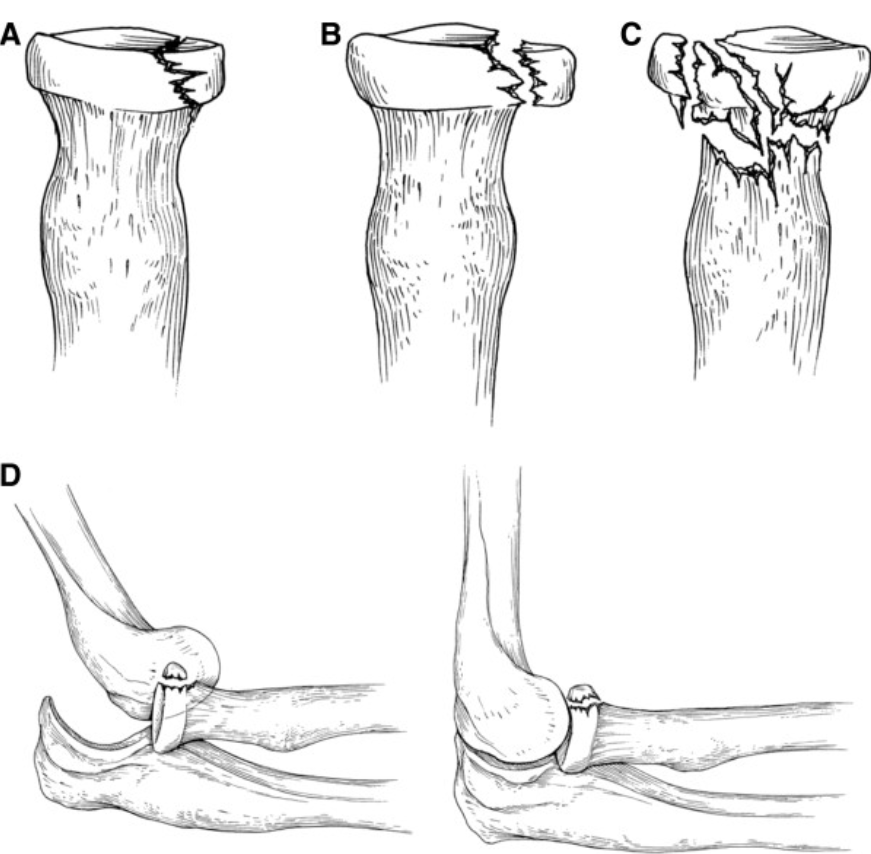

♼ 분류 (Mason 분류)

1형: 전위가 없거나 2mm 미만의 골절(그림A)

2형: 관절면 30% 이상 포함, 2mm 이상의 전위 골절(그림B)

3형: 분쇄골절(그림C)

4형: 탈구가 동반된 골절(그림D)